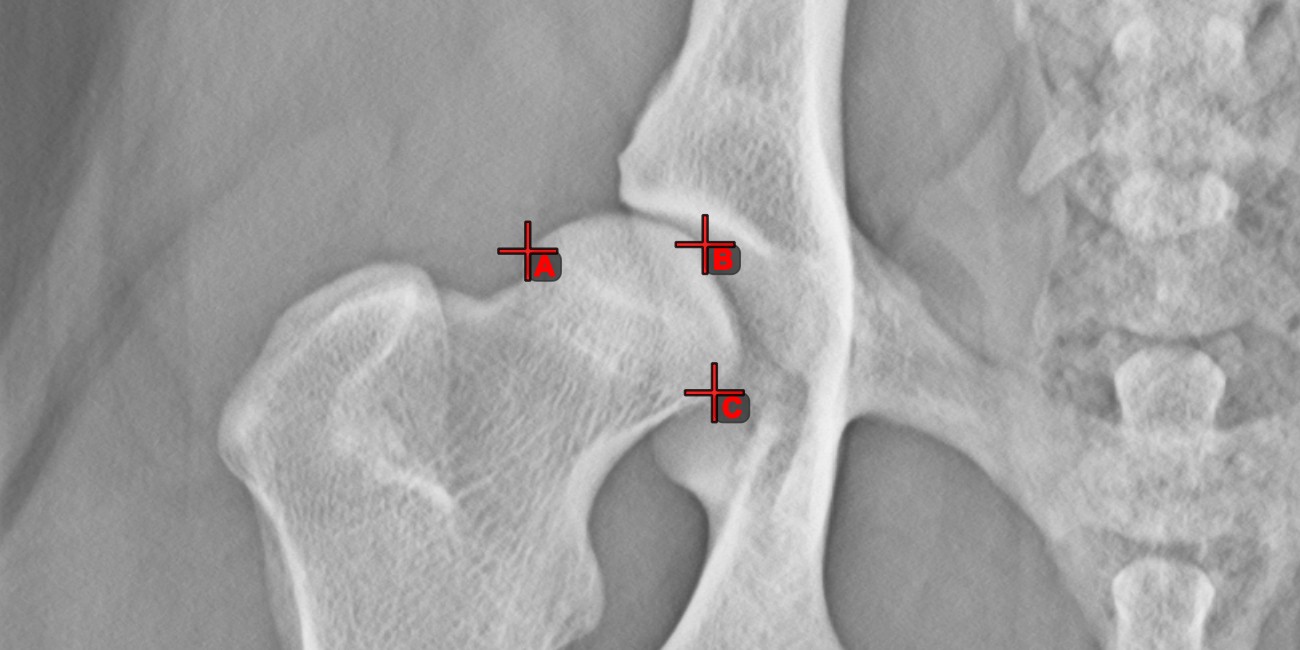

Messpunkt¶

Measurement Point. Jeder Punkt ist zur besseren Identifizierung mit einem Buchstaben versehen.Objekt auswählen/verschieben. Wählen Sie den Punkt mit der zugewiesenen Maustaste des Werkzeugs aus und verschieben Sie ihn dann frei an eine beliebige Stelle im Bild.